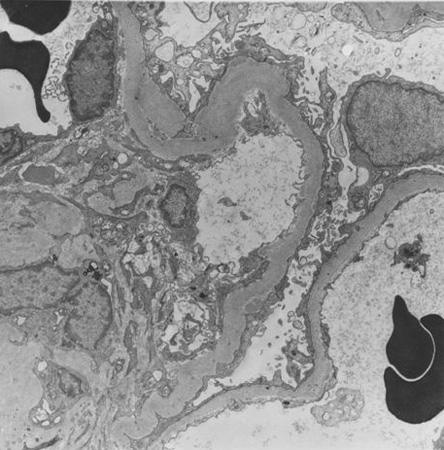

Doença renal diabética

Doença renal diabética: a expansão mesangial é geralmente reconhecida quando excede 1.5 vez a matriz mesangial normal

Do acervo do Dr. Raoul Fresco; usado com permissão